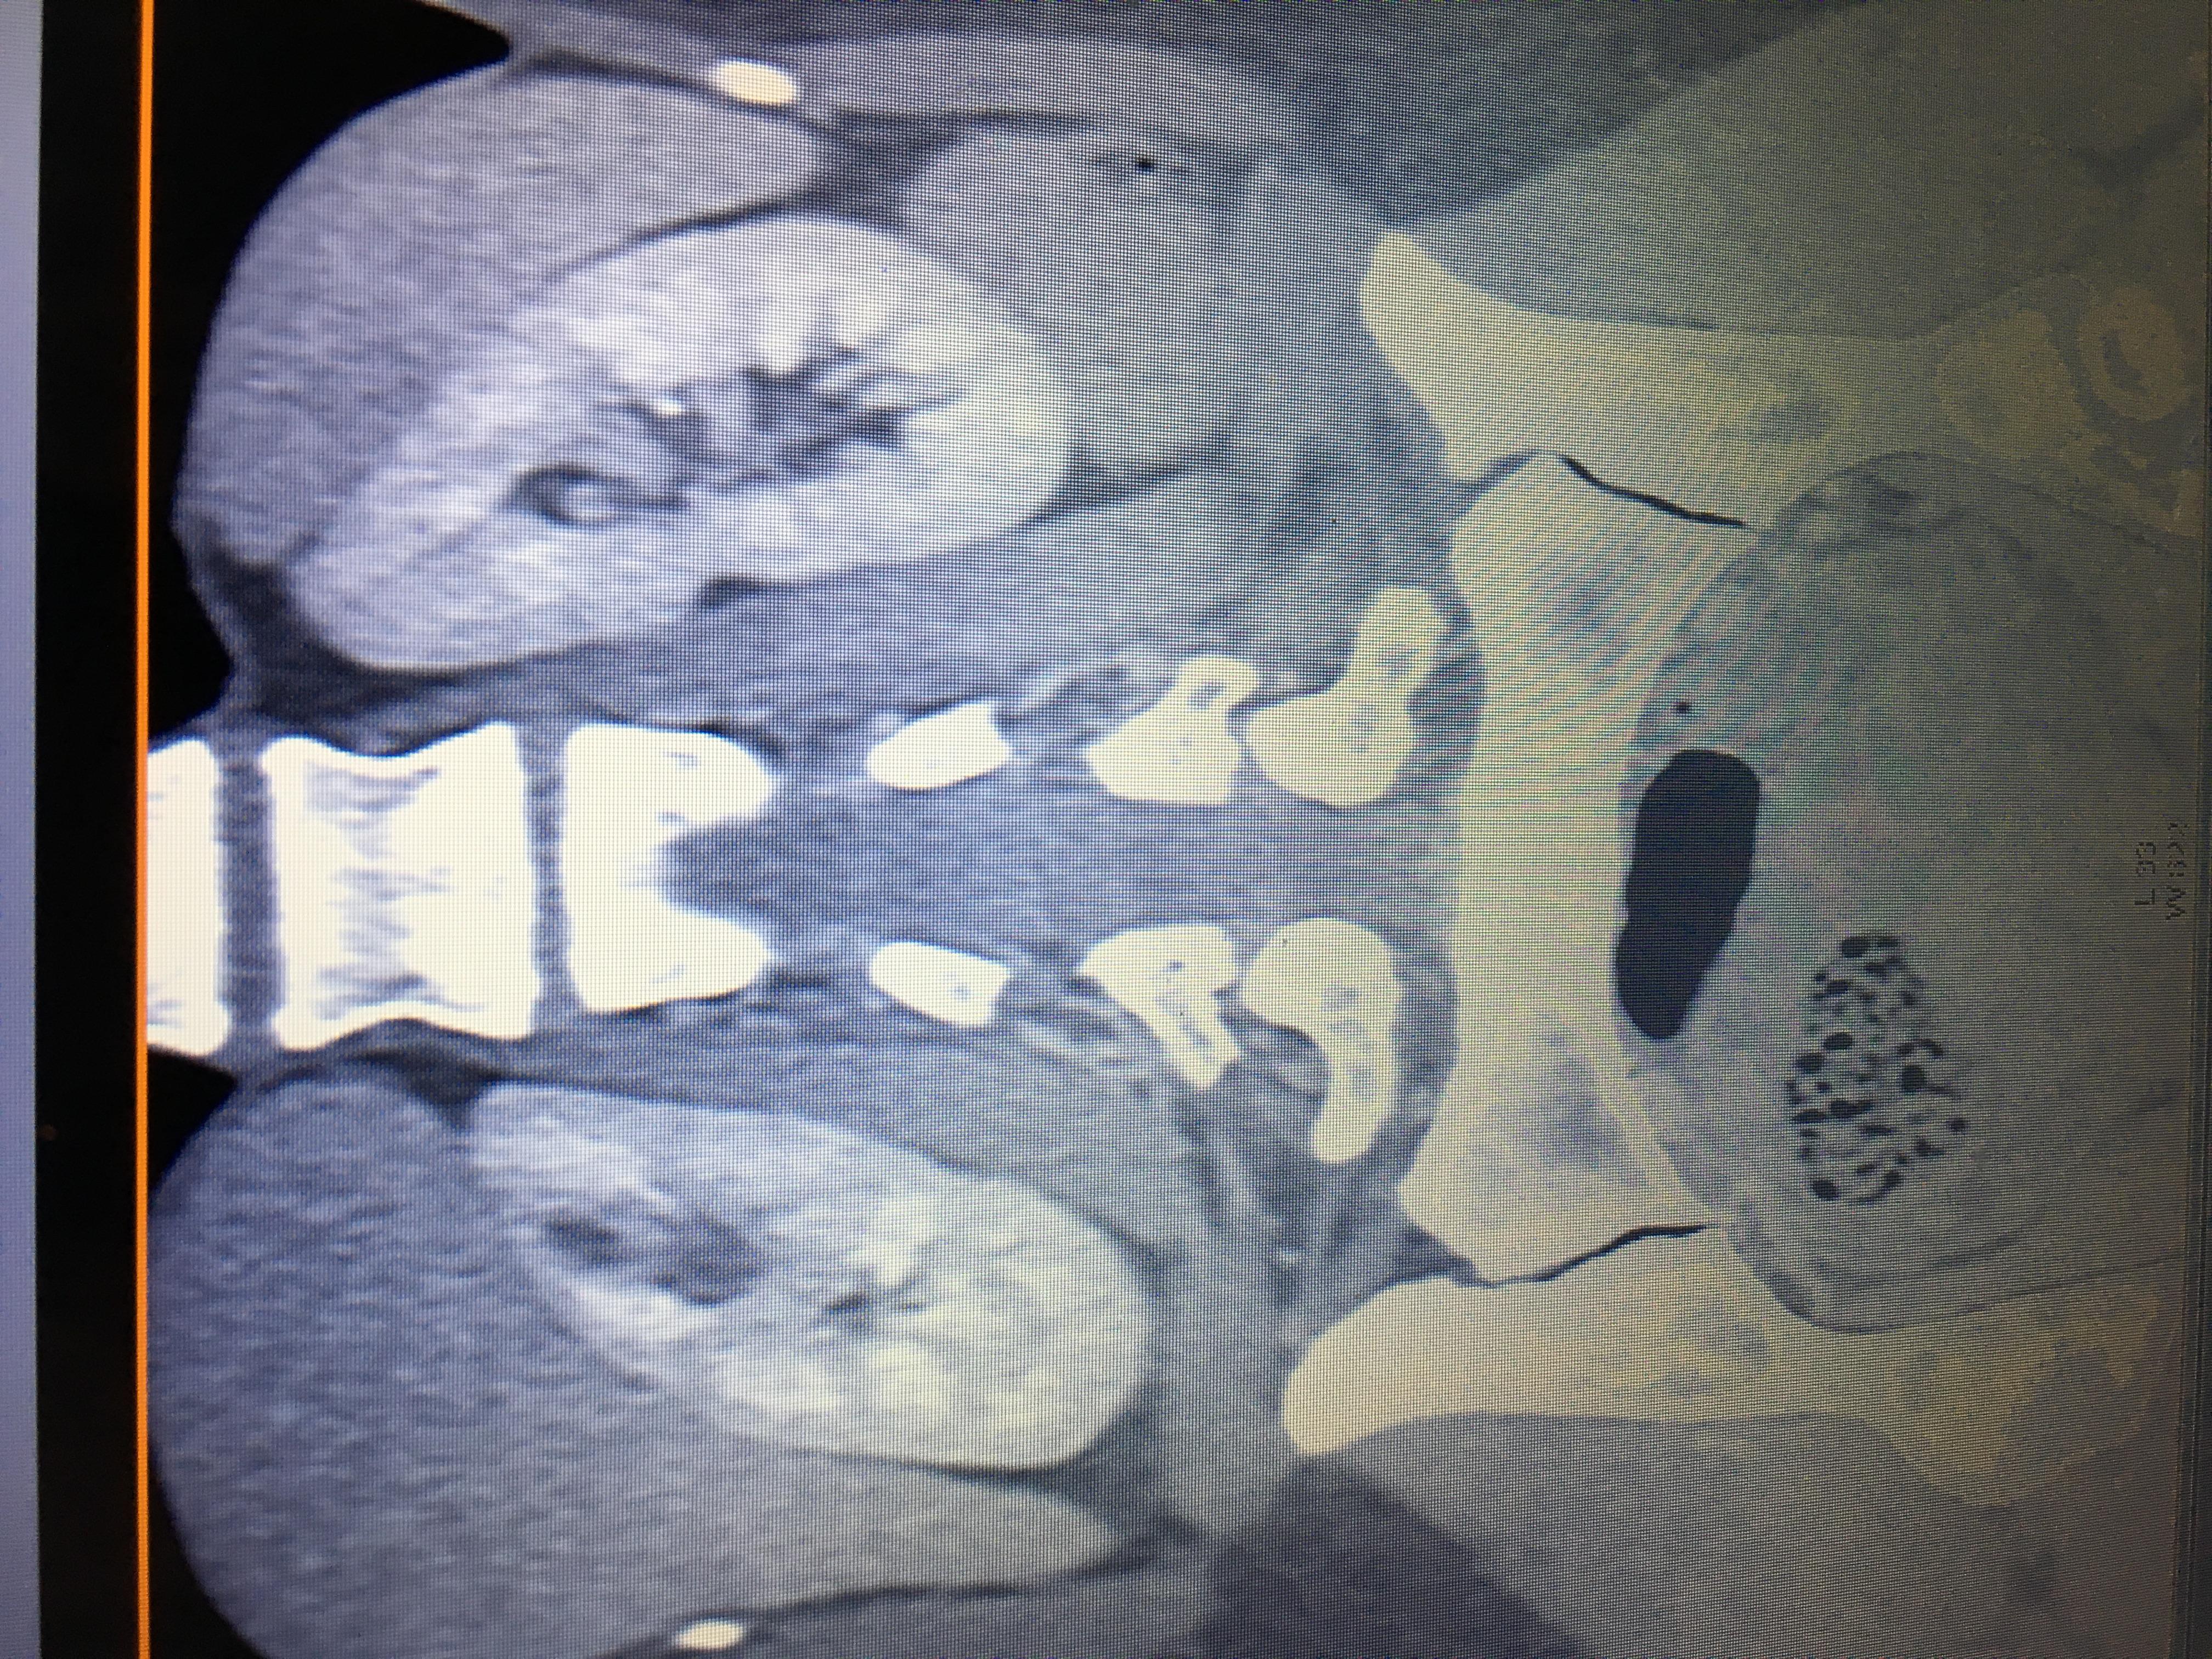

Здравствуйте,помогите, пожалуйста, с расшифровкой кт почек с контрастом. Насколько я поняла, в левой почке маленький камешек. А что за образование в правой почке? Киста с кальцинированной стенкой или камень? Спасибо за ответ!

Здравствуйте! На последнем снимке - больше данных за конкремент. Но при описании снимков должны определяться плотность образования, и нет изображения ни одного фрагмента ни одного из мочеточников. И самих снимков обычно бывает больше. Недостаточно данных для заключения.